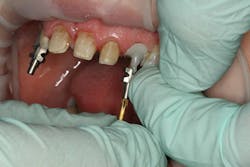

At the beginning of the impression appointment, the provisionals were approved for fit and esthetics with a particular focus on emergence profile of the implant provisionals. Profound anesthesia was achieved and the bisacrylic provisionals were removed. The preparations were cleaned with chlorhexidine (Consepsis, Ultradent) and the abutments were once again removed (figure 10). The open-tray impression copings were then tried in, their seat confirmed radiographically, and then modified into custom impression copings with flowable composite (figures 11-14). Once appropriate tissue support was confirmed, the open-tray master impression was made with a heavy and light body wash technique using vinyl polysiloxane impression material (Honigum, DMG America) (figure 15). Following the master records, the provisional abutments and bisacrylic provisionals were replaced until the seat appointment.

Figure 11

Figure 12

Figure 13

Figure 14